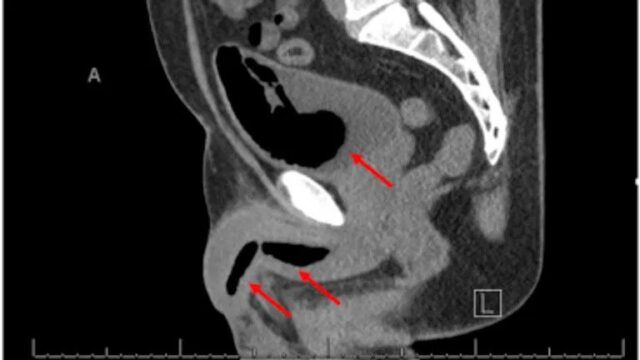

Skeniranjem su pronađene različite mase stvrdnute pjene od kojih su neke bile dugačke gotovo 11 centimetara. Sciencedirect.com

Medicinsko osoblje uspjelo je izvući ukrućenu pjenu iz muškarčeva mjehura tijekom operacije, ali mase koje se nalaze u penisu pokazale su se problematičnijima.